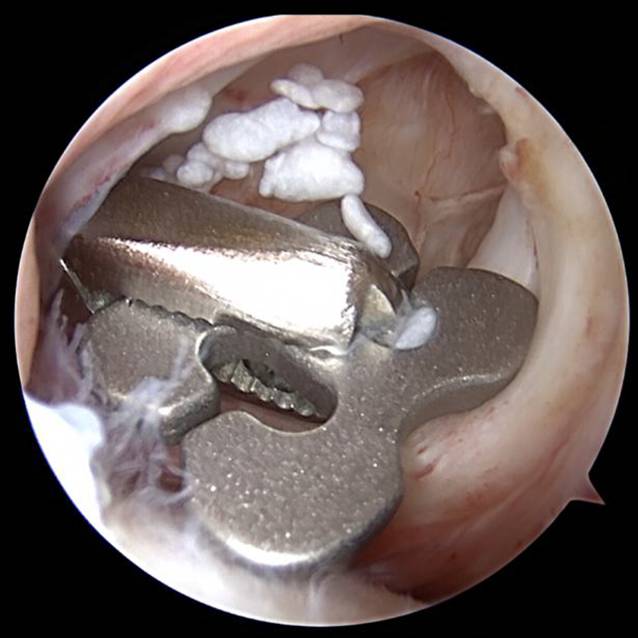

Abb. 4

Arthroskopie Schulter links: arthroskopische Bergung des dislozierten Buttons

Intraoperativ stellt sich eine ausgeprägte Synovialitis mit serösem Erguss und deutlichen Verklebungen dar. Es erfolgte eine Synovektomie und Bursektomie der Bursa subcoracoidea sowie die Entfernung multipler Knorpelfragmente (Abb. 3). Nach weiterer Präparation des Korakoids und des subkorakoidalen Raums war die Bergung des frei florierenden inferioren DogBone-Buttons ventral der Subskapularissehne möglich (Abb. 4). Anschließend konnten die Fäden und der superiore DogBone-Button mini-open dargestellt und ebenfalls geborgen werden (Abb. 5).